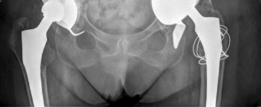

This image likely represents the immediate post-operative radiograph, clearly demonstrating the Burch-Schneider cage in situ, the cemented polyethylene liner, and the well-positioned femoral stem, with initial bone graft material visible.